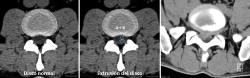

La TAC visualiza con bastante precisión el tejido óseo, siendo claramente superior a la RM para ello. También permite visualizar los tejidos blandos intra- y paraespinales, aunque la RM es muy superior en la evaluación de estos tejidos, por lo que está siendo desplazada por esta para el estudio de los problemas discales, degenerativos y radiculomedulares (Figura 11).

Al igual que en la radiología simple, muchos pacientes asintomáticos presentan imágenes anormales en la TAC. En el estudio de Wiesel et al.(25), más del 35% de las TAC de columna lumbar en personas asintomáticas eran patológicas. Por ello, los expertos advierten de la necesidad de correlacionar adecuadamente los hallazgos de la TAC con la sintomatología referida por el paciente.

La sobrevaloración de las imágenes sin una correcta valoración clínica puede conducir a errores diagnósticos y terapéuticos de importancia, oscilando desde restricciones severas de la actividad física y laboral, indicaciones terapéuticas o rehabilitadoras inadecuadas, y hasta intervenciones quirúrgicas no indicadas.